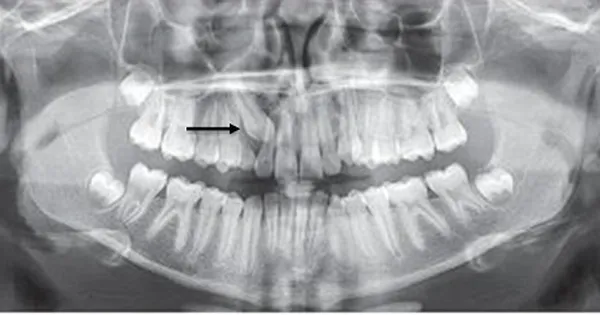

Răng 8 mọc ngầm là một hiện tượng nha khoa thường gặp, gây khó chịu và nhiều lo âu cho người bệnh. Khi nhắc đến răng 8